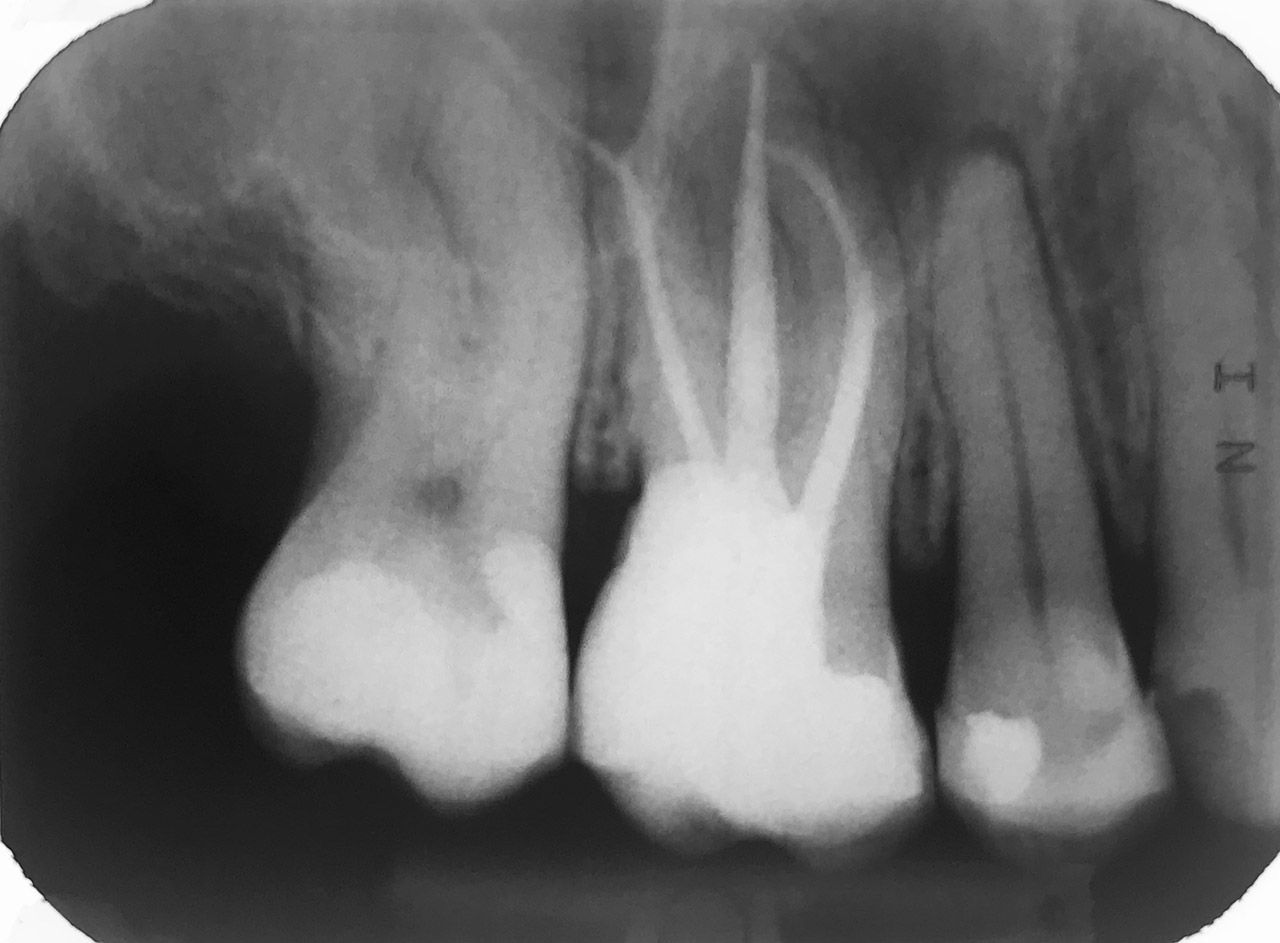

Internes und Externes Bleaching (Bleichen):

Nach Unfall mit E-Scooter unbefriedigendes Ergebnis der Erstversorgung (alio loco). Therapievorschlag: Stiftzähne?

Unsere minimalinvasive Therapie: Revision der Wurzelbehandlungen, danach internes und externes Bleaching, adhäsive Kunststoffüllungen in Schichttechnik. (Titel meiner Diplomarbeit 2003 “Die Vermeidung von Extraktion und Wurzelspitzenresektion durch zeitgemässe Endodontie in der Privatpraxis”)